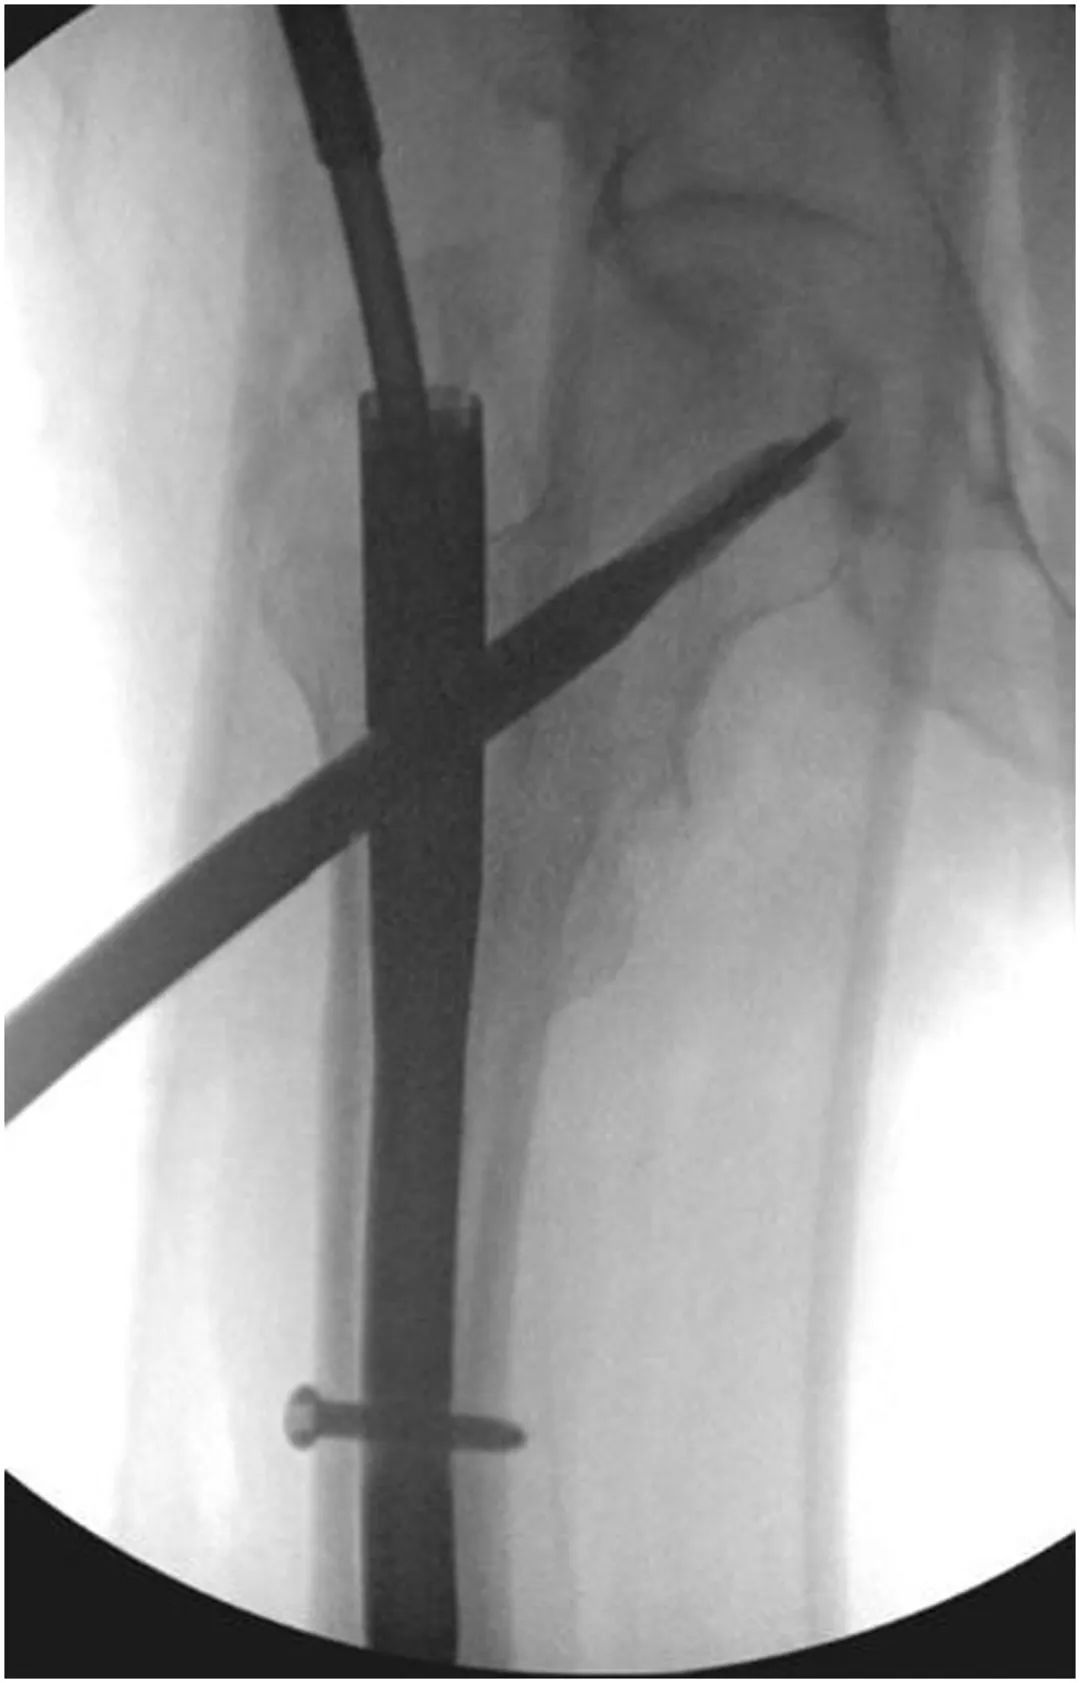

Une nouvelle vis ou lame hélicoïdale est ensuite placée dans l'os sous-chondral de la tête fémorale dans l'axe du col fémoral en veillant à ne pas pénétrer dans la tête (Figure 4).La vis est placée intentionnellement en évitant le trajet de l'ongle précédent, mais toujours pointée vers le centre de la tête fémorale.(Figure 5)

Figure 5, fluoroscopie peropératoire montrant l'insertion d'une nouvelle lame céphalo-médullaire le long du trajet du fil guide, qui a ensuite été serrée par une vis de réglage.